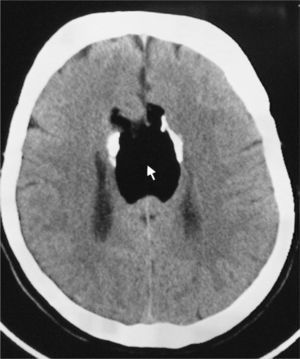

The patient visited the emergency department with symptoms of disorientation and buccofacial movements suggesting complex partial epileptic seizure. Neurological examination was normal. The cranial CT scan carried out in the emergency department (Fig. 1) showed absence of the corpus callosum and a hypodense homogeneous lesion in its location. We observed curvilinear calcifications on both sides of the lesion. Findings suggested agenesis of the corpus callosum with interhemispheric lipoma. Treatment with valproic acid was prescribed. The electroencephalogram showed epileptiform activity in the left temporo-parietal region. Brain MRI (Fig. 2) showed that the entire corpus callosum from the genu to the splenium was occupied by tissue that was hyperintense on all sequences, with the exception of the fat suppression sequence. The sagittal sequence showed bands of tissue that may correspond to remnants of the normal corpus callosum located between the lipomatous areas. We also observed slight dilation of the posterior horns of both lateral ventricles.

The appearance of the corpus callosum lipoma on the cranial CT scan is quite typical, with the low attenuation seen only in adipose tissue. In addition, it is surrounded by bilateral, rounded mural calcifications. After administration of contrast, the lesion showed no changes. In the brain MRI the lesion presents characteristics of fatty tissue, with a hyperintense signal in both T1- and T2-weighted studies.3 During complete agenesis of the corpus callosum, the lateral ventricles are far apart and never converge. They often have small frontal horns and disproportionally thick occipital horns (colpocephaly).